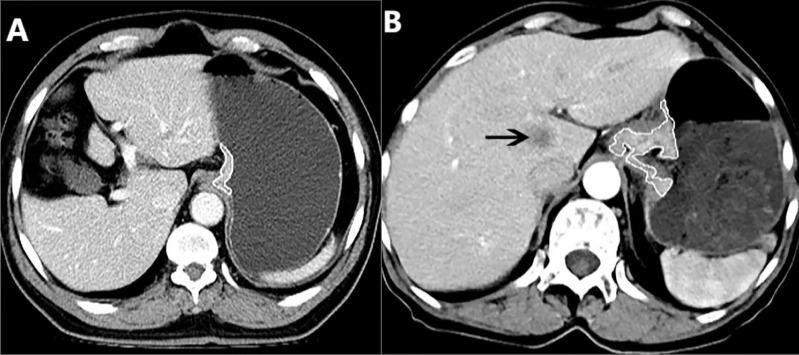

Gross tumor volume of adenocarcinoma of esophagogastric junction corresponding to cT and cN stages measured with computed tomography to quantitatively determine resectabiliy: A case control study.

To determine whether gross tumor volume (GTV) of adenocarcinoma of esophagogastric junction (AEG) corresponding to cT and cN stages measured on CT could help quantitatively determine resectability.

343 consecutive patients with AEG, including 279 and 64 randomly enrolled in training cohort (TC) and validation cohort (VC), respectively, underwent preoperative contrast-enhanced CT. Univariate and multivariate analyses for TC were performed to determine factors associated with resectability. Receiver operating characteristic (ROC) analyses were to determine if GTV corresponding to cT and cN stages could help determine resectability. For VC, Cohen's Kappa tests were to assess performances of the ROC models.

cT stage, cN stage and GTV were independently associated with resectability of AEG with odds ratios of 4.715, 4.534 and 1.107, respectively. For differentiating resectable and unresectable AEG, ROC analyses showed that cutoff GTV of 32.77 cm in stage cTN with an area under the ROC curve (AUC) of 0.901. Particularly, cutoffs of 27.67 and 32.77 cm in stages cT and cT obtained AUC values of 0.860 and 0.890, respectively; and cutoffs of 27.09, 33.32 and 37.39 cm in stages cN, cN and cN obtained AUC values of 0.852, 0.821 and 0.902, respectively. In VC, Cohen's Kappa tests verified that the ROC models had good performance in distinguishing between resectable and unresectable AEG (all Cohen's K values > 0.72).

GTV, cT and cN stages could be independent determinants of resectability of AEG. And GTV corresponding to cT and cN stages can help quantitatively determine resectability.